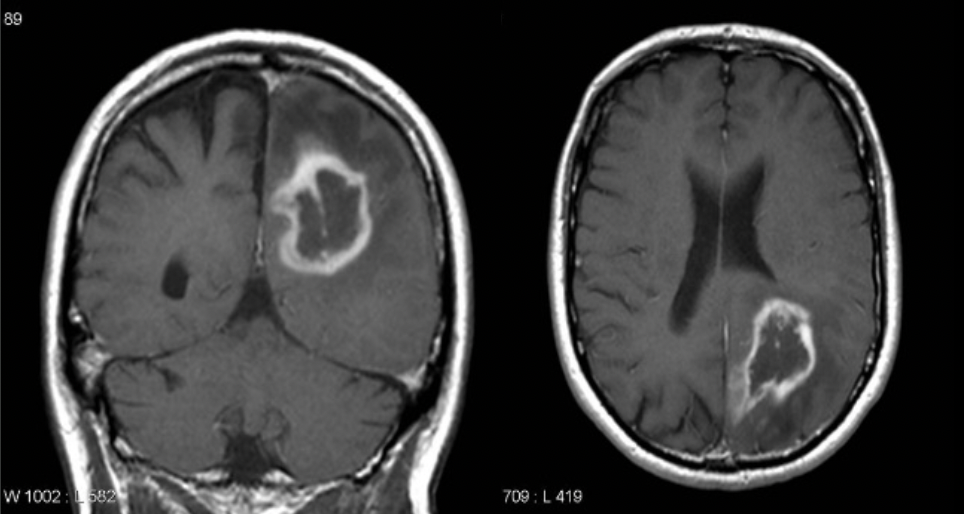

Drug Delivery Device For Treatment of Brain Tumors (2022-069)

Technology Overview

Background